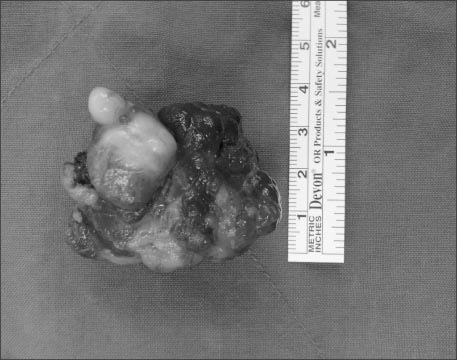

On exploratory laparotomy, a 4.5×3.5 cm sized exophytic and endophytic mass was found at the lesser curvature of the upper gastric body. A small bowel diverticulum was also found at the distal ileum and the diverticulum showed no signs of complication. Wedge resection of the stomach and diverticulectomy were performed. Histopathologically the gastric polypoid mass was confirmed to be a mature cystic teratoma (

Fig. 2,

3). He was discharged at 7 days after operation without obvious complication. There was no sign of recurrence during follow-up.

Fig. 2Gross finding shows 4.2×3.4×3.0 cm sized multi-lobulated mass, with both exo- and endophytic growth.